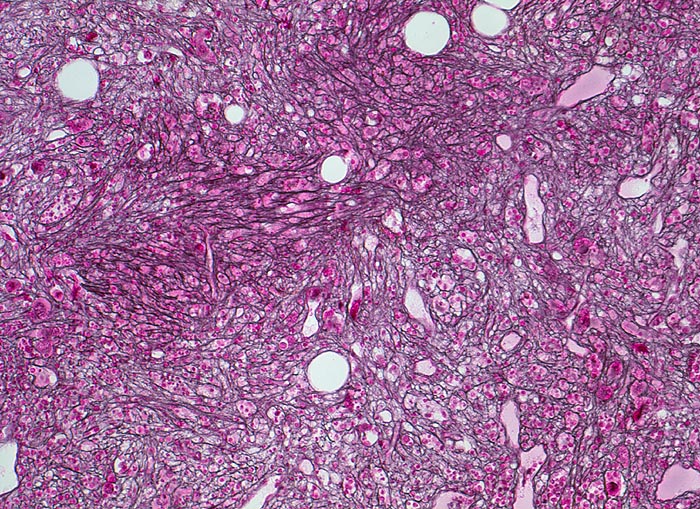

Die Erkrankung ist charakterisiert durch Knochenmarkfibrose, Hepato-Splenomegalie und extramedulläre Blutbildung. Diese findet sich am häufigsten in Leber und Milz, seltener in Lymphknoten, Nieren, Nebennieren, Dura mater, Gastrointestinaltrakt, Lunge, Mamma oder Haut. Blut und Knochenmark sind immer involviert. Die Krankheit entwickelt sich über ein initiales präfibrotisches Stadium mit hyperzellulärem Knochenmark zum fibrotischem Stadium (vorliegendes Präparat). Das fibrotische Stadium ist gekennzeichnet durch eine Vermehrung von Reticulin- und/oder Kollagenfasern und oft einer Knochenneubildung (=Osteomyelosklerose). Die Zellularität des Knochenmarks ist dann vermindert und dilatierte Marksinus enthalten intraluminale Blutbildungsherde. Es besteht eine auffallende Proliferation von Gruppen bildenden atypischen Megakaryozyten.

• Osteosklerose: verplumpte und breite Knochenbälkchen.

• Kollagenfibrose.

• Dilatierte Sinusoide mit intrasinusoidaler Blutbildung.

• Vermehrung von atypischen, in Gruppen liegenden Megakaryozyten mit abnorm lobulierten Kernen.

• Nacktkernige (zytoplasmaarme) und vergrösserte Megakaryozyten.

• Hyperplastische ausreifende Myelopoese.

• Hypoplastische Erythropoese.

• Retikulinfaserfibrose des Marks vorhanden aber in der HE Färbung schwierig quantifizierbar.